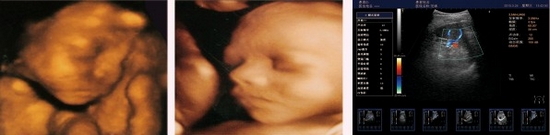

HY6000pro阿凡達雙屏三維彩色多普勒超聲診斷系統

阿凡達采用多譜勒超聲成像技術和高精度數字波束形成技術,融合組織諧波成像、斑點抑制、多波束并行等先進的圖像處理技術和高效的全數字圖文管理系統、輕松獲得更清晰的超聲圖像,專業化的測量軟件包可充分滿足臨床各種定量分析需求,靈活的配置和完全人體工學設計,提升了醫生臨床診斷的信心和臨床檢查的效率。

精確三維(3D)成像系統

全數字精確三維(3D)成像系統,采用探頭陣元切割掃描,采集大量

精確地三維數據,快速生產高分辨率、高清晰度的精確三維圖像,更

好的進一步測量和診斷。